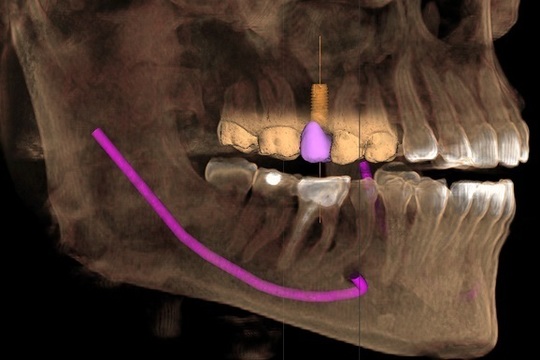

そのドイツ製システムとは、シロナ社の歯科用CT「ガリレオス」と、被せ物を自動で製作する「セレック」です。院内に専用のCTを備えることで治療前の診査・診断をより正確に行うことができ、またコンピューターでセラミックを自動で削り出すセレックを用いることで、インプラントの被せ物をより短時間で作製することができるようになっています。

それぞれの装置でデジタル化したお口の中のデータを活用し、インプラントを埋め込む位置や被せ物のシミュレーションを行えますので、より安全で自然な仕上がりのインプラント治療が可能なのです。

当院ではドイツシロナ社のセレック、歯科用CTガリレオスと連動することで院内でCTによる診査診断ができセレックによりインプラントの被せ物が作製できるようになりました。

セレックの口腔内印象をガリレオスのCTデータと重ね合わせインプラントの埋入位置の確認と被せ物のシュミレーションをします。

セレックとガリレオスのシュミレーションにより出来た外科用ガイドです。これにより最終的な被せ物の位置を考慮し外科的に安全な位置にインプラントを埋入することができます。